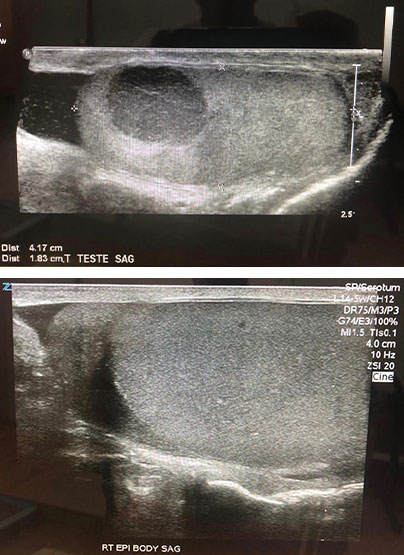

In the spring of 2012, at age 41, I was diagnosed with a cancerous tumor called a "classic seminoma" (a form of testicular cancer). Tumor markers and tissue samples confirmed this diagnosis. The doctors at Sloan Kettering and Mt. Sinai Medical Center wanted to remove the tumor and follow up with chemo and radiation. However, given my history of ulcerative colitis, they – and I – were very concerned that my body was not going to react well to the chemo and radiation – and the immune-suppressing drugs I was taking for the colitis would be problematic with such treatment. I was left in a quandary: do I just do the surgery and not the follow up chemo and radiation, which puts me at risk of it spreading to other locations? Or do I have the surgery, chemo, and radiation and risk the ulcerative colitis? I didn't like either option.

What I had learned from Dr. Fuhrman is that if you give your body the right foods, and care for your body through exercise and rest, that your body will be able to heal itself and transform itself in ways you never imagined, and that even things like cancer and ulcerative colitis can disappear. Within only a few weeks of adopting these dietary changes my body began to transform. My energy level, clarity of mind, and overall physique made dramatic changes for the better. Sonograms of the tumor, taken that summer, showed that it was beginning to shrink in size and I began pulling myself very slowly and gradually off the medication for the ulcerative colitis because I was, for the first time since I was 15, feeling no symptoms in my gut. Fortunately, I found an amazing immunologist who monitored my progress and supported my efforts. Eventually I was able to completely remove myself from medicine for the colitis and the tumor shrank to nothing. I was able to rid myself of cancer and ulcerative colitis without any of the conventional treatments and without any of the side effects associated with it. Along with that, my overall health has so greatly improved it is hard to fully quantify the before and after results.